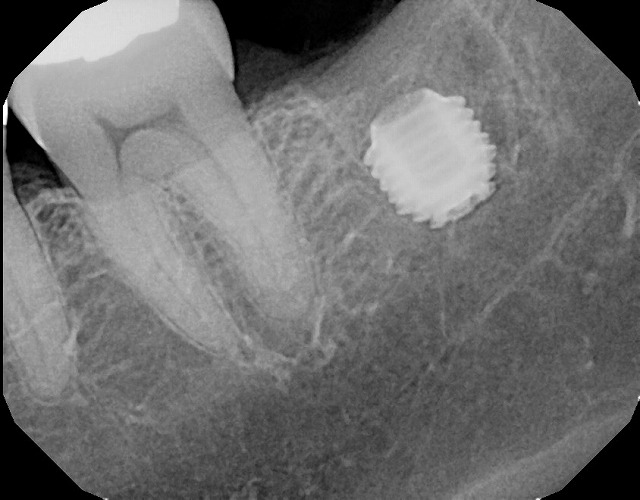

これがレントゲン写真です。治療前の写真と

治療後の写真です。